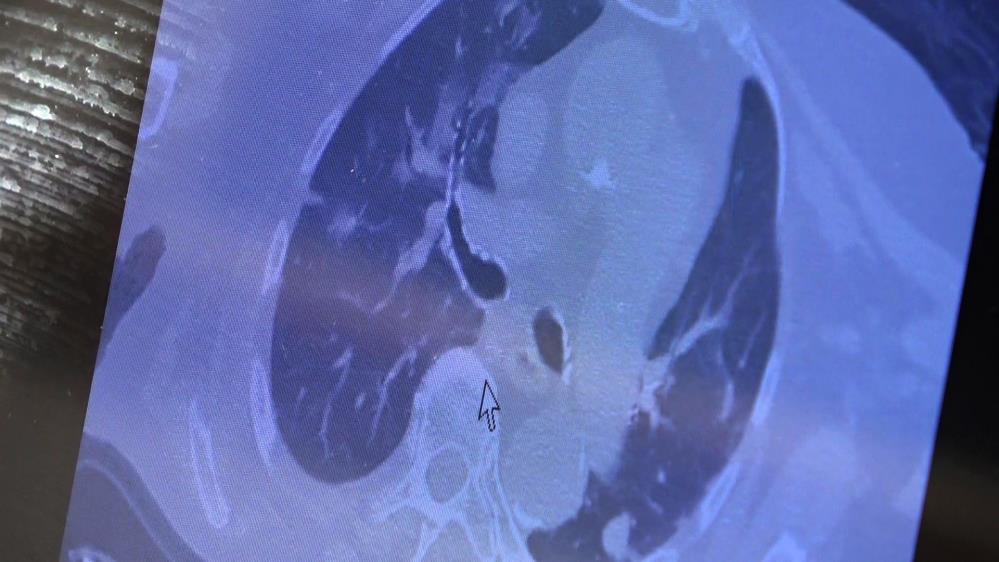

81 yaşında akciğer tutulum olan hastanın tomografisi

Karşılaştıkları bu yeni hasta profilini örnek vererek açıklayan Özkaya, "81 yaşındaki bir hasta. Ailesinde kovid pozitif biri varken panik yaparak aşıya gidiyor. Sonrasında hızla akciğer tutulumu olan bir hasta ile karşılaşıyorsunuz. Bu şekilde ailenizde pozitif biri varsa ve kendinizde halsizlik kırgınlık hissediyorsanız panik yapmadan önce doktora gitmenizi sonra aşı olmanızı istiyoruz. Şu an ‘aşı oldum hastalandım’ diyenlerin büyük bir kısmı subklinik olarak virüsle enfekte iken aşı olan grubu oluşturuyor" şeklinde konuştu.